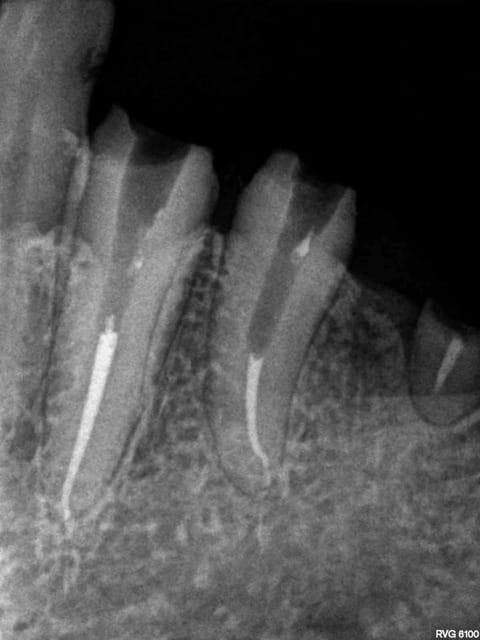

X ray 03 medium zvq18j - Eugenol

cyber_quenottes

13/10/2014 à 17h18

par contre là tu as bien 14 à 15 secteurs

soit près de 110 € de clichés